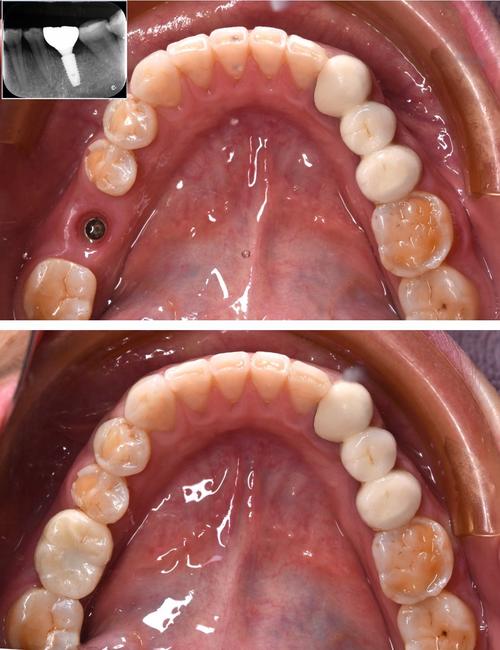

即刻种植指拔牙后立即在新鲜拔牙窝内植入种植体,减少手术次数;即刻负重则是在种植体植入后,同期安装临时牙冠,实现“即种即用”。

- 微创结合:这两种技术常与数字化导板联合,利用微创切口植入种植体,减少手术创伤,前牙区拔牙后,若牙槽骨条件允许,通过即刻种植可避免拔牙后3-6个月的等待,且微创操作能最大限度保留牙龈形态,美观效果更佳。